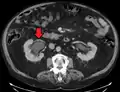

Hydronephrosis due to a kidney stone at the ureteral vesicular junction seen on CT scan

The choice of imaging depends on the clinical presentation (history, symptoms and examination findings). In the case of renal colic (one sided loin pain usually accompanied by a trace of blood in the urine) the initial investigation is usually a spiral or helical CT scan. This has the advantage of showing whether there is any obstruction of flow of urine causing hydronephrosis as well as demonstrating the function of the other kidney. Many stones are not visible on plain X-ray or IVU but 99% of stones are visible on CT and therefore CT is becoming a common choice of initial investigation. CT is not used, however, when there is a reason to avoid radiation exposure, e.g. in pregnancy.[11][12]